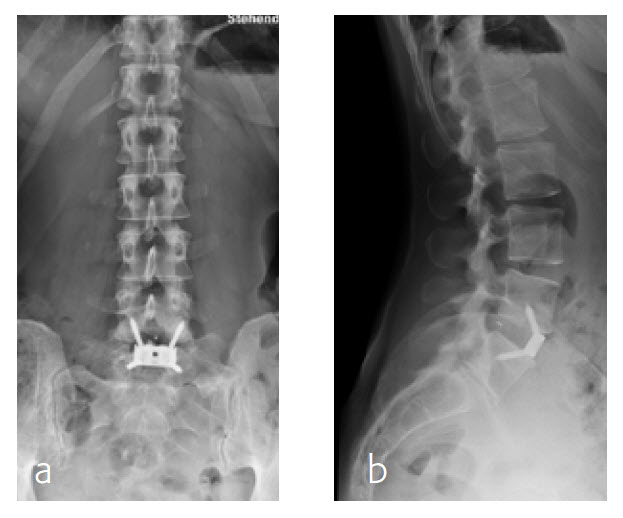

6-month follow-up

By the planned 6-month follow-up, the patient was pain free and fully active. Evaluation with CT scans was undertaken, consolidation was starting (Fig 8).